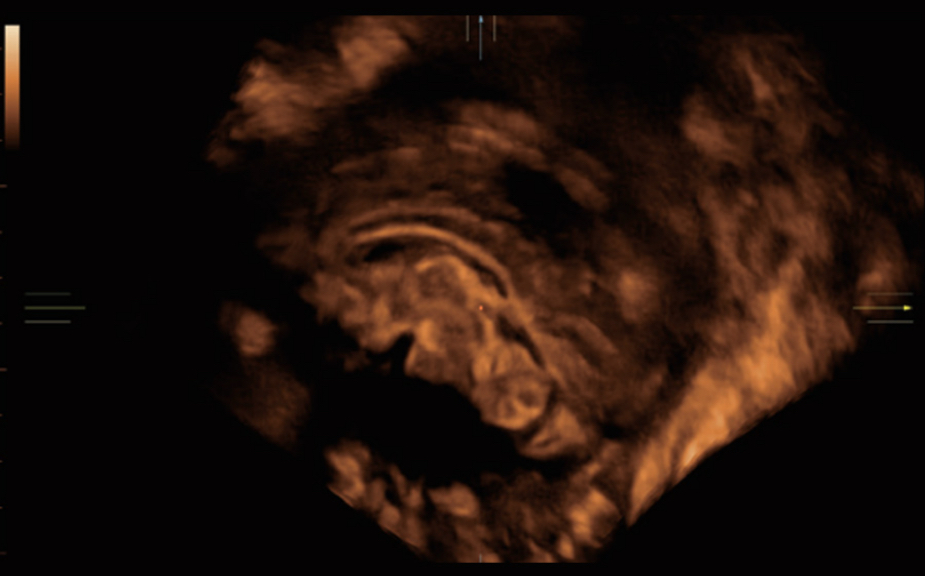

De Nuewa I9, speciaal ontworpen voor vrouwen en neonatale gezondheidszorg, biedt een innovatieve ervaring van binnenuit. Deze innovaties zijn ontwikkeld op basis van diepgaande inzichten in complexe klinische scenario's en bieden nauwkeurige en tijdige antwoorden, evenals een uitstekende effici?ntie en opmerkelijke gebruikerservaring.

Het ZST+ platform is een buitengewone innovatie en revolutie in de wereld van ultrasound. Het transformeert ultrasoundgegevens van conventionele bundelvorming naar kanaalgegevensverwerking. Het overwint de traditionele afweging tussen ruimtelijke resolutie, temporele resolutie en weefseluniformiteit, en levert een uitzonderlijke beeldkwaliteit voor oneindige beeldvormingsoplossingen met non-stop verbeteringen.